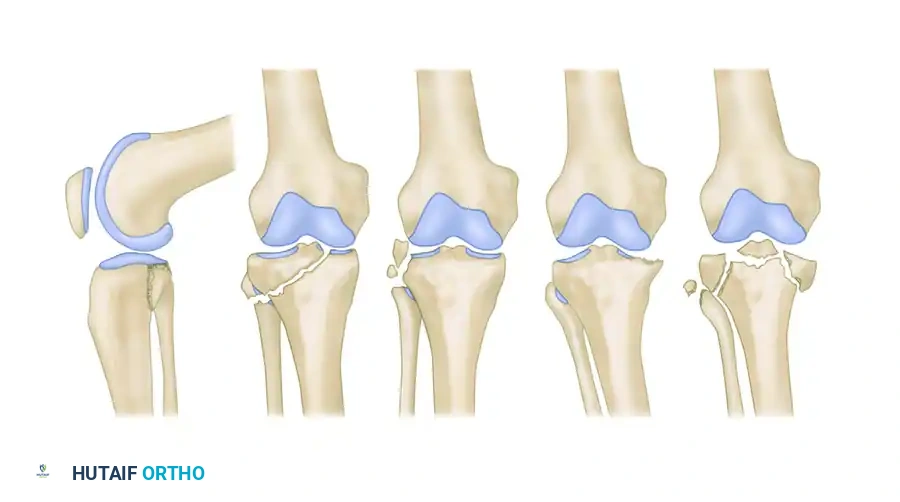

THE HOHL AND MOORE CLASSIFICATION SYSTEM

The Hohl and Moore classification system divides proximal tibial fracture-dislocations into five distinct morphological types. Understanding these patterns is critical for preoperative planning, anticipating soft-tissue injuries, and determining the optimal surgical approach.

Type I: Coronal Split Fracture

Accounting for approximately 37% of all tibial plateau fracture-dislocations, the Type I pattern is characterized by a coronal split.

* Pathoanatomy: The fracture primarily involves the medial side and is most apparent on the lateral radiographic view. The fracture line runs at a 45-degree angle to the medial plateau in an oblique coronal-transverse plane.

* Associated Injuries: The fracture may extend to the lateral side. Avulsion fractures are highly common, frequently involving the fibular styloid, the insertion of the cruciate ligaments, and Gerdy’s tubercle.

Type II: Entire Condyle Fracture

Constituting 25% of all fracture-dislocations, the Type II injury involves the shearing of an entire condyle.

* Pathoanatomy: This fracture may involve either the medial or lateral plateau. It is distinguished from standard plateau fractures and Type IV injuries by a fracture line that extends into the opposite compartment, passing directly beneath the intercondylar eminence.

Type III: Rim Avulsion Fracture

Type III injuries account for 16% of fracture-dislocations and are characterized by high-energy avulsions.

* Pathoanatomy: This type involves almost exclusively the lateral plateau. It presents as avulsion fragments of the capsular attachment, Gerdy’s tubercle, or the peripheral articular rim.

Type IV: Rim Compression Fracture

Accounting for 12% of all fracture-dislocations, the Type IV pattern is driven by severe subluxation and impaction.

* Pathoanatomy: The tibia subluxates to such an extent that the femoral condyle violently compresses a portion of the anterior, posterior, or "middle" articular rim of the tibia.

Type V: Four-Part Fracture

The most devastating of the classifications, the Type V injury constitutes 10% of all fracture-dislocations.

* Pathoanatomy: This is a true bicondylar fracture-dislocation where both tibial plateaus are split off, and the intercondylar eminence is a separate, free-floating fragment. The distinguishing feature is the complete dissociation of the articular surface from the metaphysis and diaphysis.